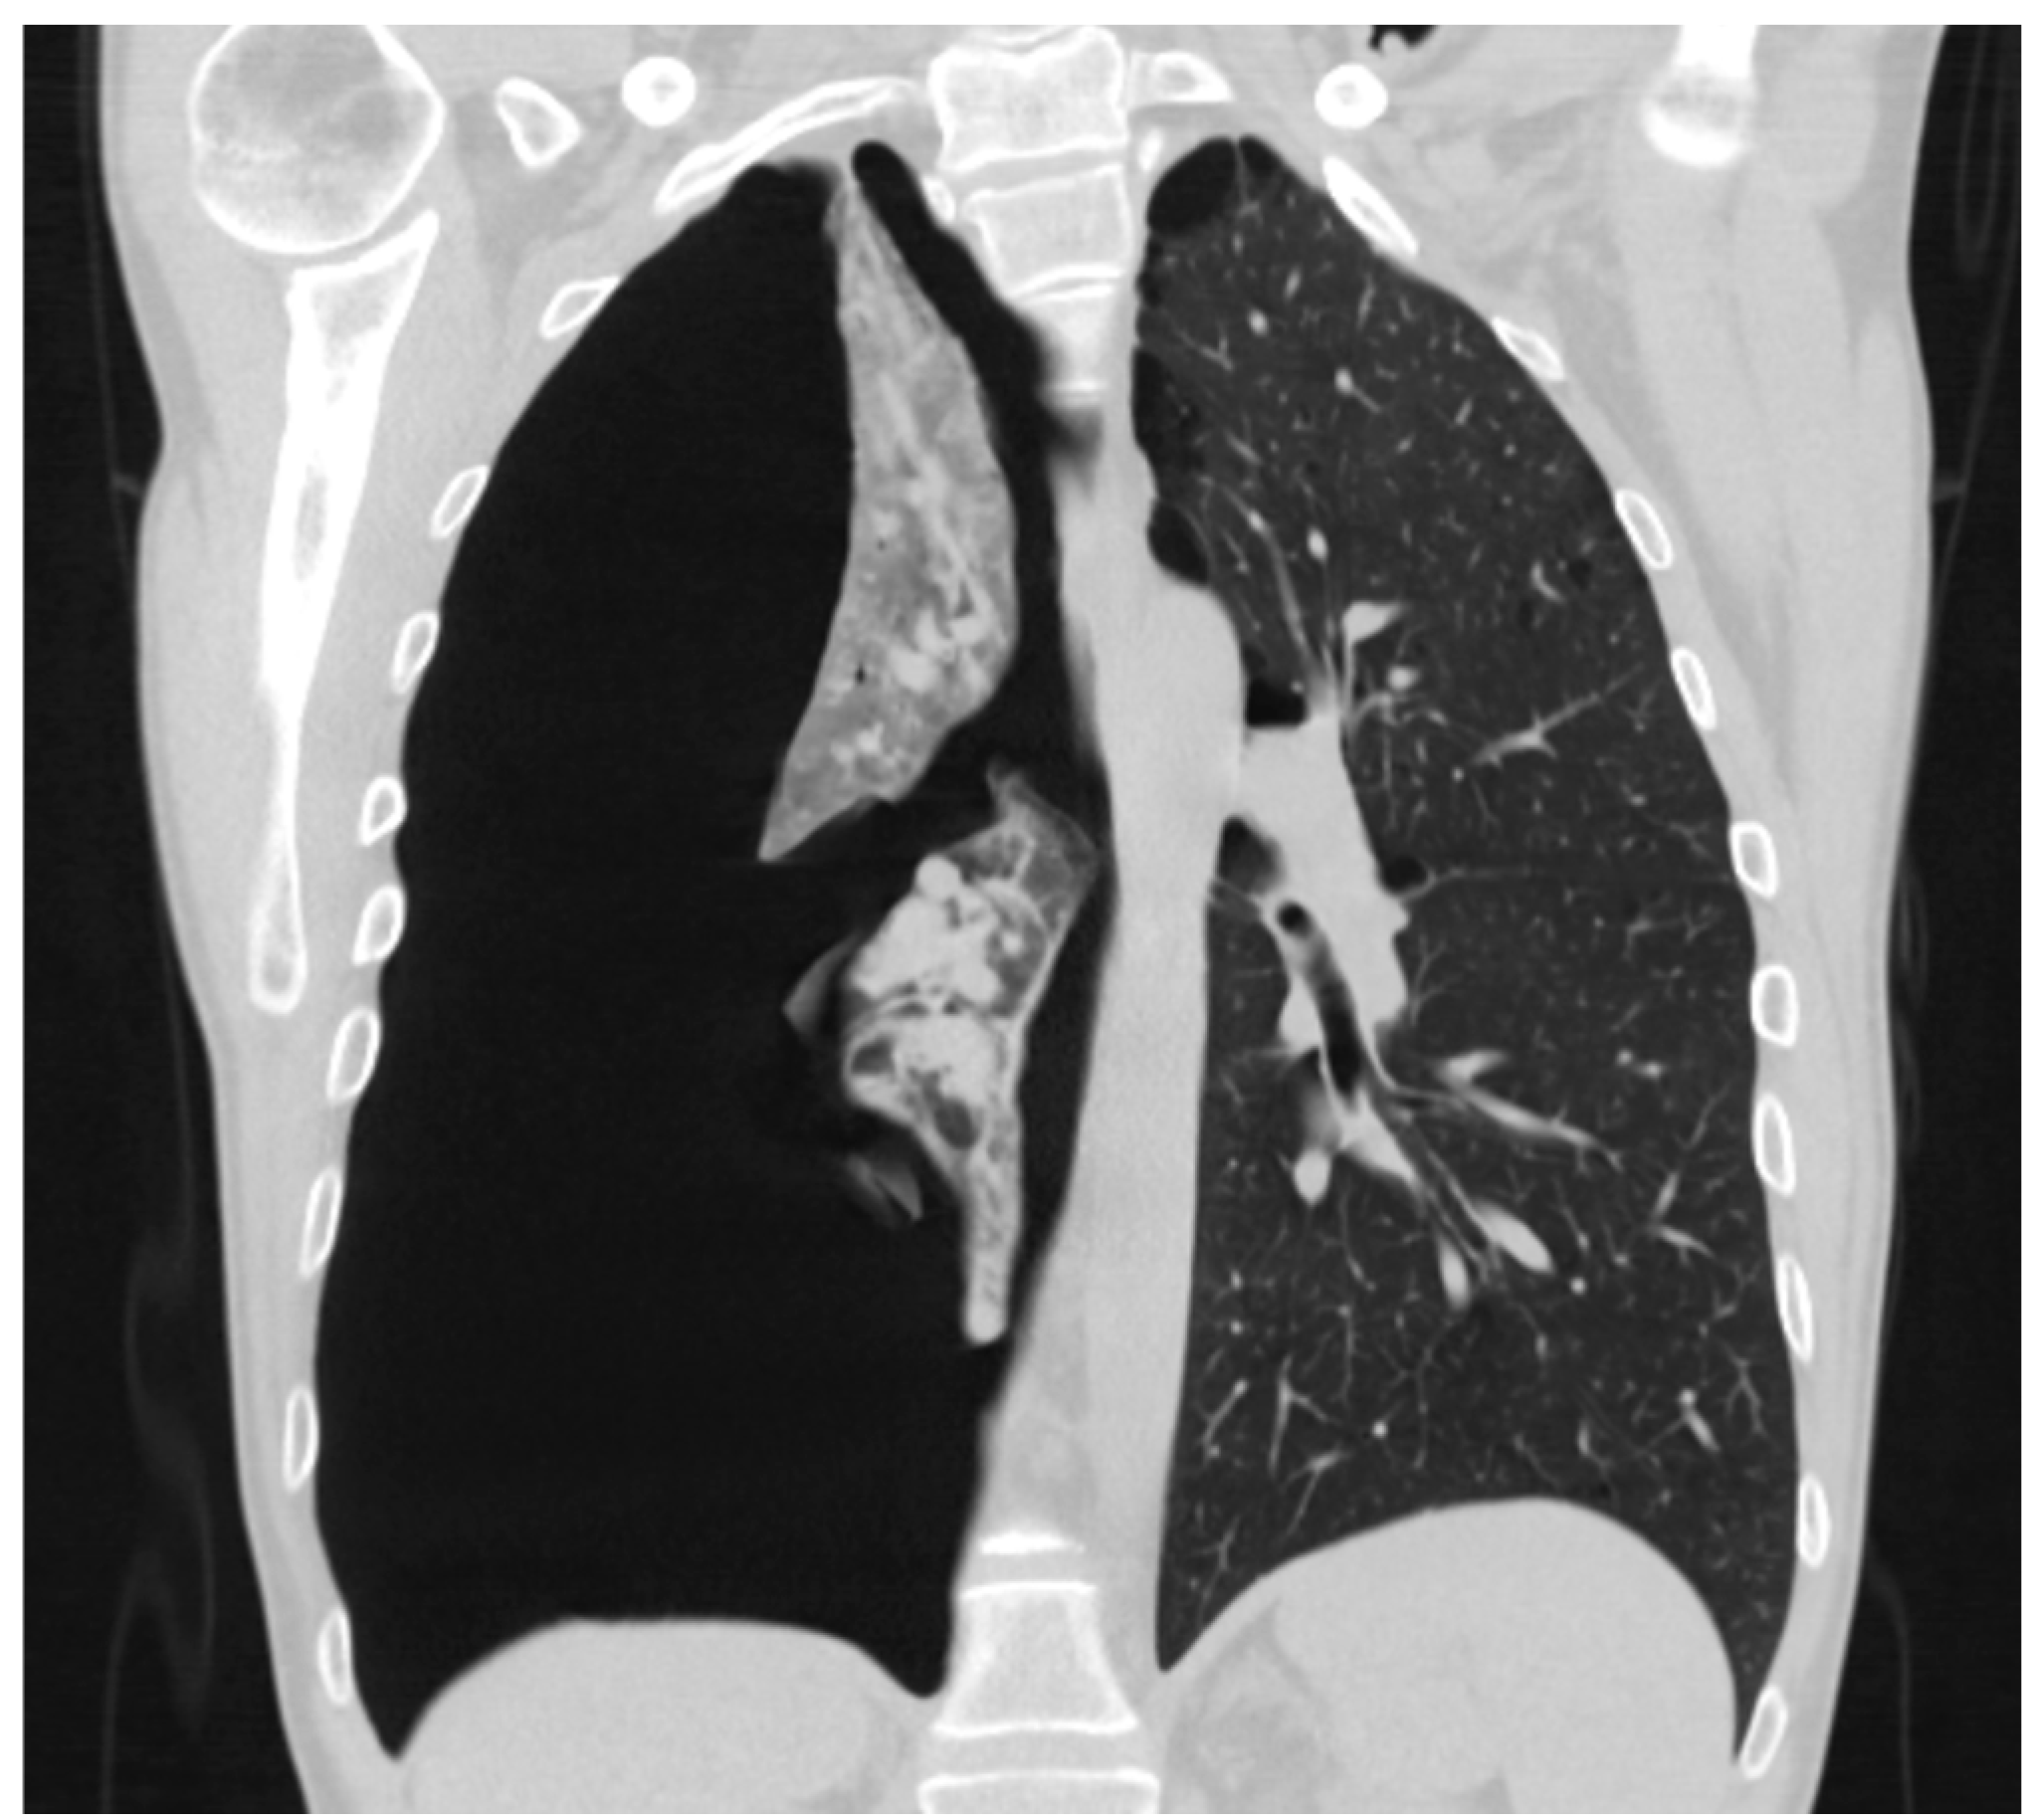

3.4. Computed Tomography Scan

3.5. Size of Pneumothorax